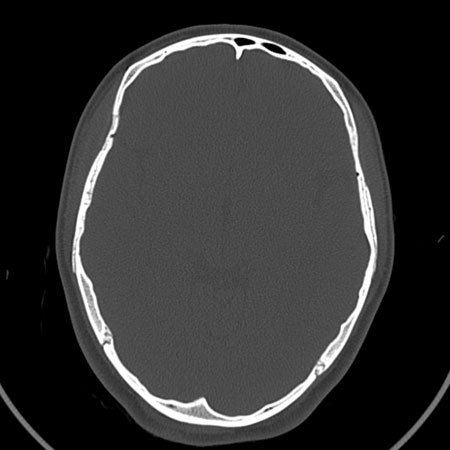

请问各位战友:图示箭头处是否为颅骨骨折?

病史:患者,女,20岁.头部及腹部外伤20分钟.伤后昏迷,无呕吐.头及右侧腰背部疼痛,双侧瞳孔等大,

右肾区叩痛.其它无异常.患者家属否认原有外伤史.

请大家看看是否为颅骨骨折.还是正常变异,或为陈旧骨折.谢谢.

ct 扫描发现枕骨变异一例

温毅,张瑞萍,张延林,尹涛

患者男,19 岁。因头部外伤就诊。体检:营养、发育良好,五官对称,外观无畸形。右额部见局部皮肤青紫,无皮肤破损。ct 扫描:脑组织及颅外软组织未见异常;骨窗见枕骨中下部,由枕骨内、外隆凸至枕骨大孔处有一线样长约27 mm裂隙(图1、2),宽约1 .0 mm。边缘光滑、硬化,贯穿枕骨内外板。颅骨无

凹陷及移位征象。

讨论: 胚胎学研究证实,枕骨发源于脊椎而不是颅骨,在胚胎形成40 ~ 42 体节时,前部5 个体节形成

枕骨。枕骨基底部和鳞部各有一个骨化中心,还有两个枕骨外侧部[1],分别出现于胚胎的第7 周及第8 周。本例枕骨枕鳞部骨缝可能与枕骨各骨化中心发育障碍有关。经枕骨隆凸至枕大孔处骨缝变异极为罕见,易误诊为骨折,细致观察骨缝边缘是否有硬化和软组织是否肿胀即可与骨折相鉴别。

枕骨骨折,另外一处不考虑骨折

上图

箭头1:骨缝

箭头2:骨折不能排除